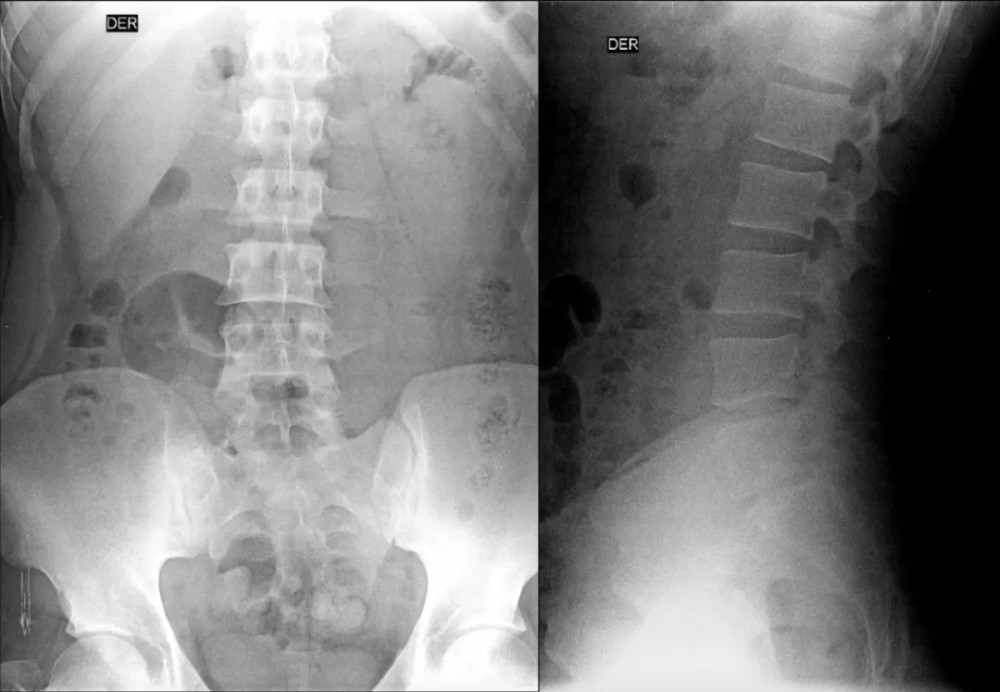

文章插图

L5 双侧横突肥大 , 间隙变窄 , 假关节形成 , 为 Ⅱb 型;